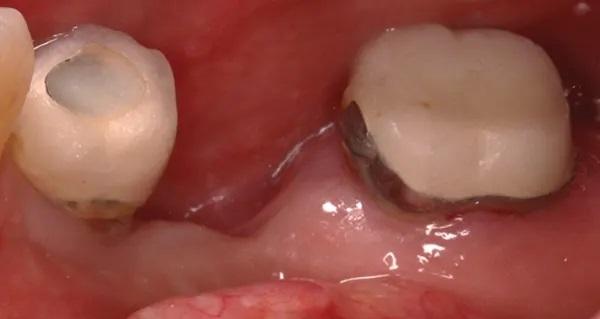

Во время консультации в 2016 году при внутриротовом осмотре выявлено большой обьем потери как вертикальной, так и горизонтальной резорбции (класс III по Зайберту) 12 мм в области отсутствующего имплантата 4.5 (фото 3 – фото 5), в области имплантата зуба 4.4. диагностировано обнажение четырех витков имплантата с дистальной стороны и двух витков с щечной стороны.

Фото 4. Демонстрирует зону потерянного имплантата 4.5 с язычной стороны.

Фото 5. Показывает окклюзионный вид альвеолярного отростка в зоне отсутствующего имплантата, стрелками обозначена вертикальная и горизонтальная убыль костной ткани и подлежащих мягких тканей, прободение щеки в области дефекта и ограничение досягаемости ороговевших тканей.